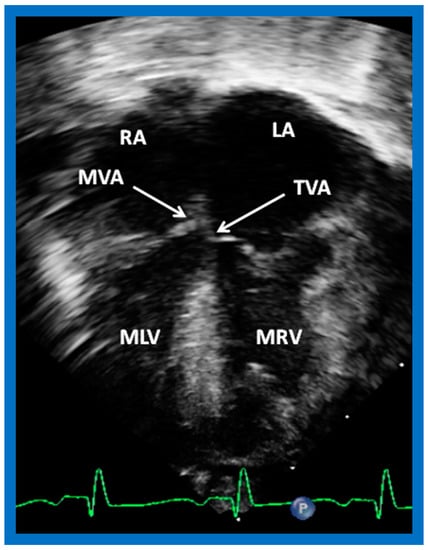

Atrioventricular Valve Attachments to the Septum

The attachments of the AV valve leaflets to the interventricular septum have a characteristic pattern. In subjects with the normal left to right ventricular relationship, attachment of the tricuspid valve to the interventricular septum is at a lower level than that of the medial leaflet of the mitral valve (Figure 38A,B). On the contrary, in patients with ventricular inversion, the valvar attachments to the interventricular septum are reversed with the right-sided AV (morphologic mitral) valve attachment higher than the left-sided AV (morphologic tricuspid) valve attachment (Figure 39).

Figure 39. Selected echo image in the apical four-chamber projection of a child with ventricular inversion. Note the superior level of mitral valve attachment (MVA) on the right side relative to the attachment of the tricuspid valve (TVA) on the left side, signifying that the ventricles are inverted. This is a reversal of what is illustrated in Figure 38. Left atrium (LA), morphologic left ventricle (MLV), morphologic right ventricle (MRV), and right atrium (RA) are labeled. Replicated from reference [4].